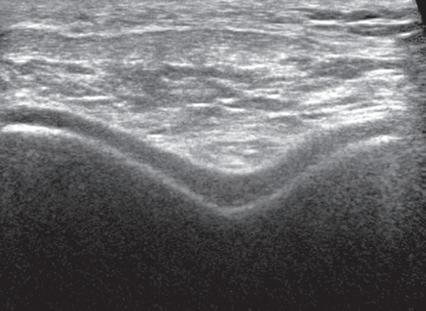

FIGURE 1.11 Anisotropy. Ultrasound images of distal supraspinatus tendon in long axis (S) shows an area of hypoechoic anisotropy (curved arrow) (A), where the tendon fibers become oblique to the sound beam, which is eliminated (B) when the transducer is repositioned so that the tendon fibers are perpendicular to the sound beam. H, Humerus.